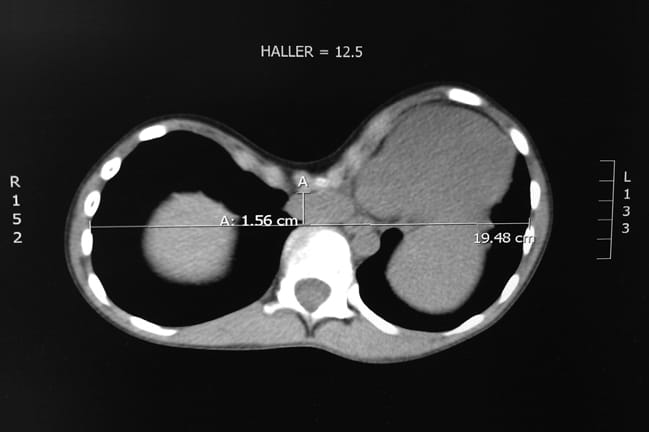

Study gives pediatric surgeons objective guidelines for advising parents on pectus surgery.